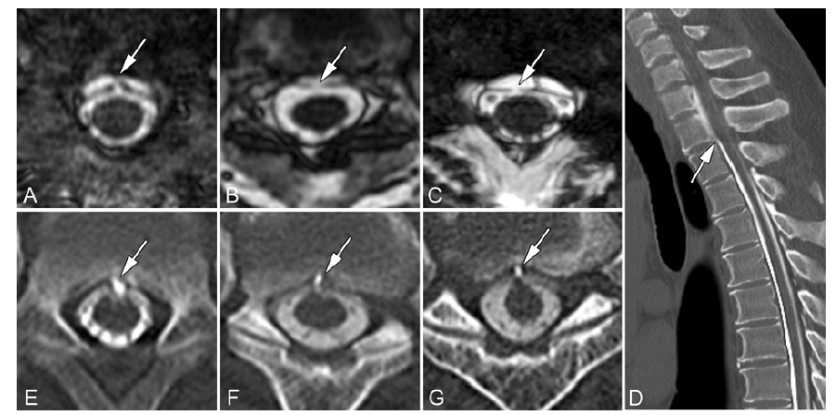

图2. A-C.术前FIESTA MRI轴向成像显示,病例8(A)、12(B)和19(C)的硬脊膜缺损(箭头)。E-G.术前CT脊髓造影轴向成像显示,病例9(E)、11(F)和18(G)与硬膜缺损相关的微球(箭头)。D.病例20动态CT矢状位的硬膜外造影剂(箭头)。确定渗漏部位的患者进行相应水平定向EBP;对未确定渗漏部位的患者则在腰椎水平进行非定向EBP。通过17号硬膜外腰穿针,注入4:1比例的自体血和造影剂的混合物。如EBP不能持续有效,进行手术修复硬脊膜缺损。